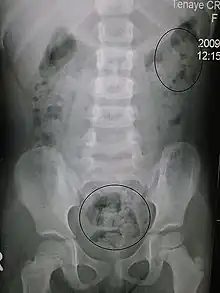

In order to correctly manage neurogenic bowel dysfunction it is important to accurately diagnose it. This can be done by a variety of methods, the most commonly used would be taking a clinical history and carrying out physical examinations which may include: abdominal, neurological and rectal examinations.[17] Patients may use the Bristol Stool Chart to help them describe and characterise the morphological features of their stool, this is useful as it gives an indication of the transit time.[18] An objective method used to evaluate the motility of the colon and help with diagnosis is the colon transit time.[19] Another helpful test to diagnose this condition may be an abdominal X-ray as this can show the distribution of feces and show any abnormalities with the colon, for example a megacolon.[14]